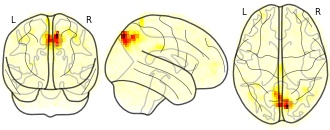

"name": "Multi_VBMgreater_fMRIenhanced",

"description": "Multi-modal analysis in BPD. Brain regions exhibiting greater gray matter and enhanced activation during emotion processing in BPD compared to healthy controls. Note: Results were thresholded at p<.0025. Note2: Results were updated (see Erratum for this publication).",